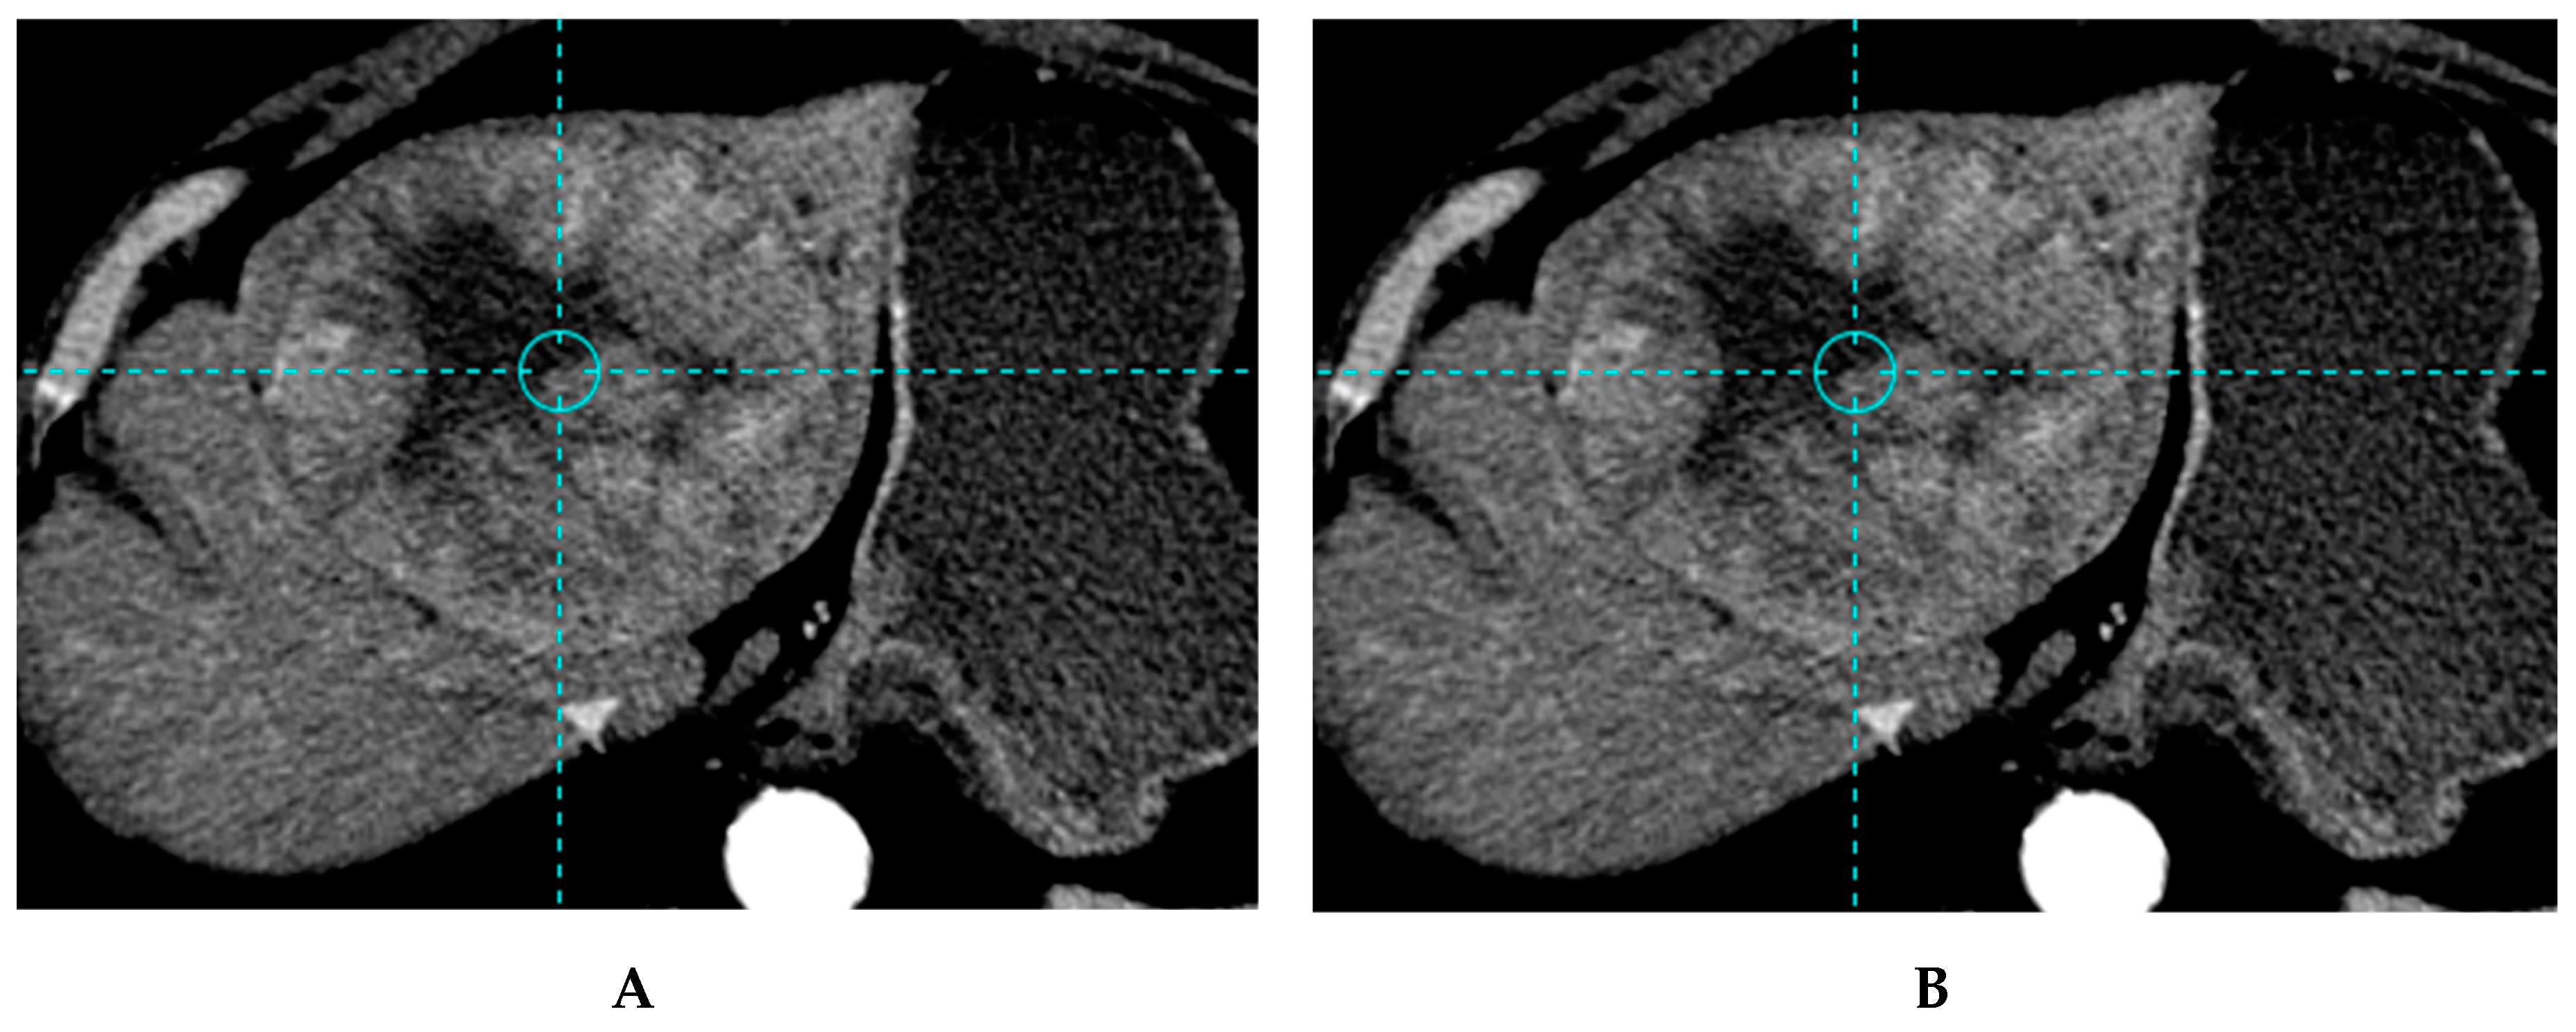

2.4.1. Segmentation